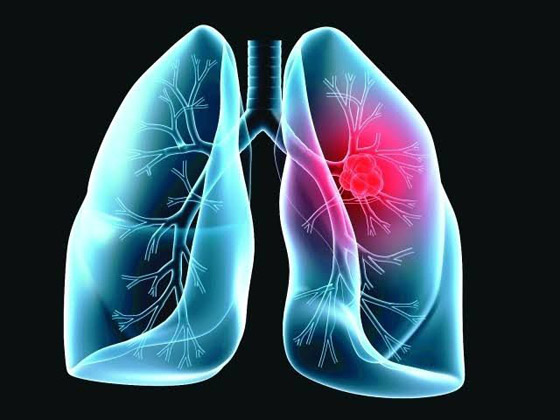

حذر أطباء متخصصون من أن تورم الوجه قد يكون علامة رئيسية على الإصابة بسرطان الرئة. يحدث تورم الوجه عندما يضغط الورم على الوريد الأجوف العلوي (SVC)، الذي يربط الرأس بالقلب، إذ يشير الأطباء إلى أن أغلب حالات انسداد الوريد الأجوف العلوي (SVCO) ناتجة عن سرطان الرئة.

ولفت الأطباء إلى أن معظم حالات انسداد الوريد الأجوف العلوي ناتجة عن سرطان الرئة أو انتشار المرض إلى الغدد الليمفاوية القريبة، بحيث تصبح منتفخة.

أعراض مالوفة

كما كشف الخبراء بالمجال أنه بالإضافة إلى تورم الوجه، قد يحصل تورم في الرقبة والذراعين وأعلى الصدر بسبب ضغط الوريد. كما تشمل الأعراض المصاحبة الأخرى ضيق التنفس أو الصداع أو تغيرات في البصر، أو ظهور أوردة زرقاء على الصدر أو الدوخة. وسرطان الرئة نادر الحدوث لدى من تقل أعمارهم عن 40 عاما، ويؤثر في الغالب على كبار السن.

ودعا أطباء إلى الإقلاع عن التدخين فورا كونه السبب الرئيسي، حيث تشير إحصائيات علمية إلى أن المدخنين يتصدرون الإصابة بهذا المرض بنسبة 70% من الإصابات.